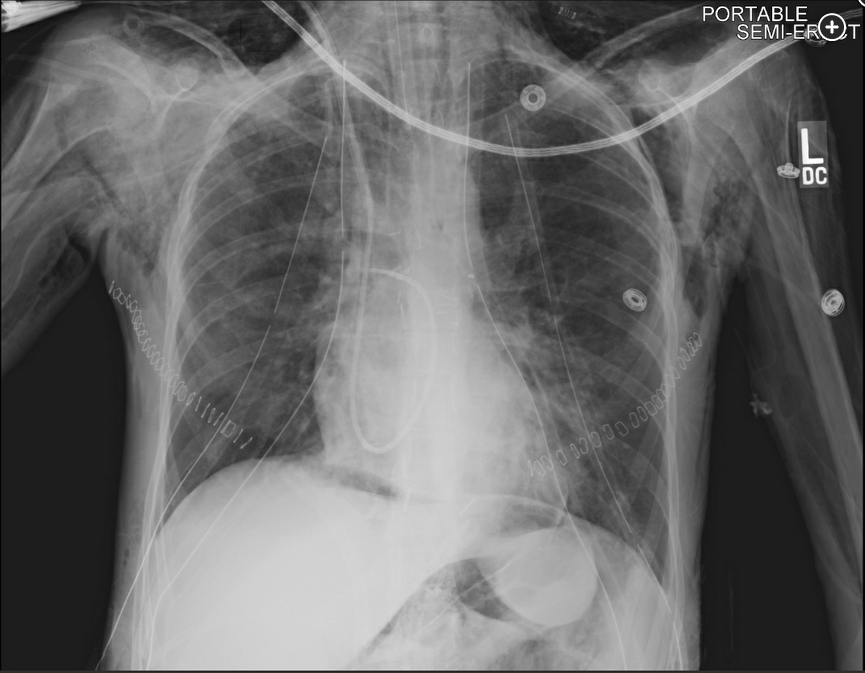

The chest radiography shows pneumomediastinum, which should suggest the possibility of anastamotic dehiscence. Pneumoperitoneum is also present.

Bronchoscopic visualization of the airway anastomosis should be performed to confirm the diagnosis, assess the severity of the defect, or exclude an anastomotic dehiscence. Dehiscence, the separation of the surgical anastomosis (Figure 2), is an infrequent complication after lung transplantation; however, it must be suspected when a lung transplant recipient develops a pneumothorax or pneumomediastinum in the early postoperative period.

Airway complications occur in 7% to 18% of lung transplant recipients, with a related mortality of 2% to 4%. Airway complications are typically divided into early (<3 months) and late (>3 months) complications. Early airway complications include anastomotic infection, necrosis, or dehiscence. The incidence of anastomotic dehiscence ranges between 1% and 10%, with severe dehiscence reported in 2% of lung transplant recipients. Anastomotic dehiscence has been primarily attributed to ischemia of the donor bronchus in the first 1 to 6 weeks after transplantation. During lung transplant surgery, the airway anastomosis is performed between the bronchus of the donor lung and the bronchus of the recipient lung. Notably, the donor bronchial artery circulation is interrupted during the lung procurement procedure, and it is not routinely revascularized. As such, revascularization of the donor’s bronchus by the recipient’s bronchial arteries may take 2 to 4 weeks, placing the donor bronchus at risk for ischemia. Additionally, preoperative and postoperative pulmonary infections are significant risk factors for airway complications, and anastomotic infections increase the risk of dehiscence. Anastomotic dehiscence can present with dyspnea, pneumomediastinum, subcutaneous air, pneumothorax, persistent air leak, and the inability to wean from mechanical ventilation.

As management is dependent on the severity of the dehiscence, one must first assess the severity of the defect via direct bronchoscopic visualization prior to determining the best management strategy. Partial dehiscence is often treated conservatively with observation and close bronchoscopic surveillance, along with antimicrobial therapy. In cases of severe anastomotic dehiscence, deployment of temporary, self-expanding metal stents via bronchoscopy have been shown to facilitate healing. If bronchoscopic interventions fail, surgical interventions, such as open repair for reanastomosis, flap bronchoplasty, transplant pneumonectomy, or retransplantation may be considered. Anastomotic dehiscence is associated with a high mortality, and most patients die from infections and complications secondary to the dehiscence. His pneumoperitoneum is a result of his pneumomediastinum and should be managed conservatively.123456